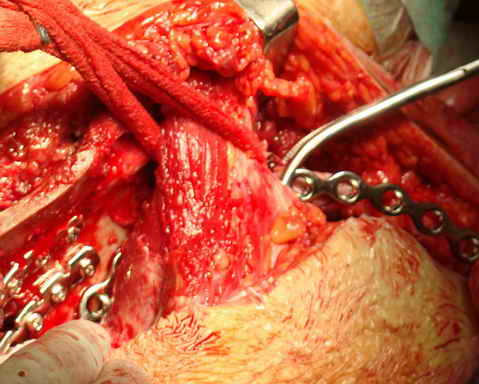

Остеосинтез подвздошной кости

Укладка тазовой пластины "matta"

Операционная. Оперирует д.м.н. проф. Казанцев А.Б.